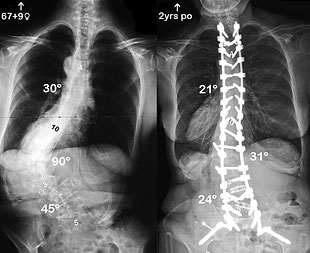

I went to see my doctor because of the intense pain I was experiencing in my back and down my legs. Seeing the x-rays of my spine, I was dumbfounded at the degree of curvature. The 91-degree protruding curve gave me trouble, as I was constantly irritating it by bumping against things. However, to my surprise, my doctor said that I had to have both hips replaced before the spinal surgery could be done.

It is now two and a half years since my spinal surgery (posterior spinal fusion of thoracic vertebrae 2 to sacrum 1), which was preceded with bilateral hip replacement surgery. I now look and feel like a new person – 5-ft. 4-in. tall, physically healthy, and virtually without pain.